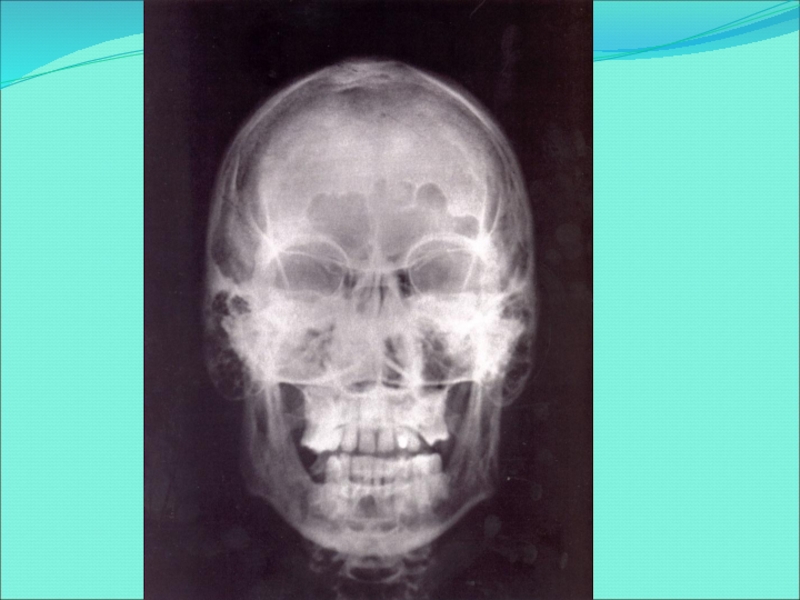

Слайд 44A. Мужской череп массивнее и тяжелее женского. Женский череп округлее

и сужается сверху. B. Глазные впадины у женщин более резкие и

четкие, а у мужчин - округлые и имеют скругленные края. C. Скуловая кость у мужчин более выпуклая. D. Челюсть у женщин более округлая, а у мужчин - квадратная. E. Мужчины имеют более мощный череп. F. Надбровные дуги у мужчин большие и выпуклые.

G. Подбородок у мужчин объемнее и выступает под тупым углом, у женщин - под острым